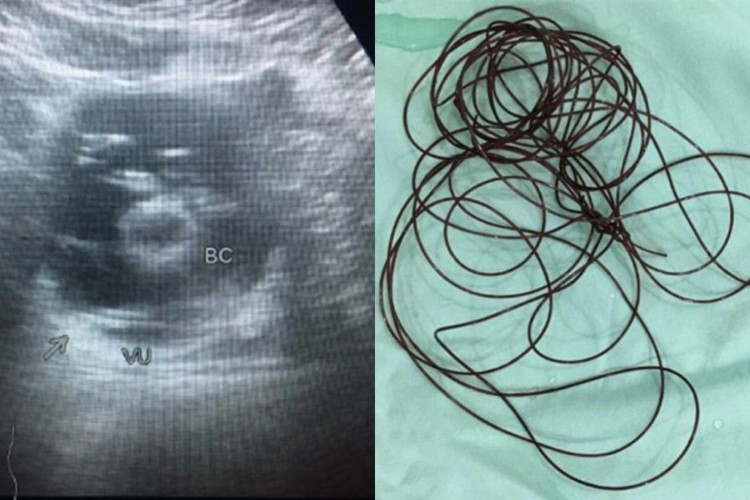

Um homem de 37 anos precisou ser internado após inserir 2 metros de uma linha de nylon no próprio pênis. O caso foi atendido no Hospital-Geral Acadêmico Dr. Soetomo, em Surabaya, na Indonésia, e publicado pela revista científica Radiology Case Reports. O homem era virgem e teria realizado a ação para obter prazer sexual durante a masturbação.

O indonésio chegou ao hospital alegando sentir fortes dores no abdômen. Diagnosticado com Transtorno Obsessivo Compulsivo (TOC), ele explicou que enfiou o fio pela uretra quando seu pênis estava ereto enquanto assistia pornografia.

Após introduzir a linha no órgão, o homem alegou que passou a sentir dificuldades para urinar e, quando conseguia, percebia a presença de sangue.

O procedimento de cistoscopia foi realizado para a retirada da linha do pênis do paciente. Apenas com anestesia local, o fio de nylon foi removido com a ajuda de uma pinça. O homem teve alta dois dias depois sem maiores problemas.